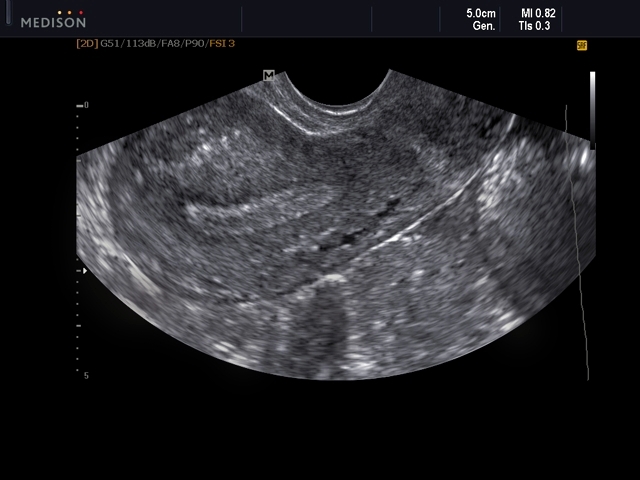

Как было сказано выше, основным диагностическим методом для данного состояния является УЗИ. При этом врачи УЗИ называют такую структуру линейной. Связано это с тем, что тогда как сами слои (базальный, функциональный и эпителиальный) имеют очень низкую эхогенность, границы между ними имеют эхогенность очень высокую. В результате они четко визуализируются на УЗИ в виде линий, разделяющих слизистую на три слоя.